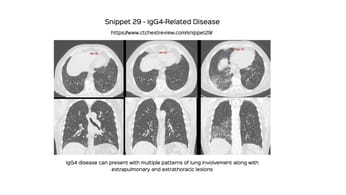

This 70-years old lady presented with non-resolving bilateral lung masses, showing consolidation and ground glass.

The video explains the differential, what was done and the final diagnosis, with a review of a recent Aug 2021 paper on this subject.